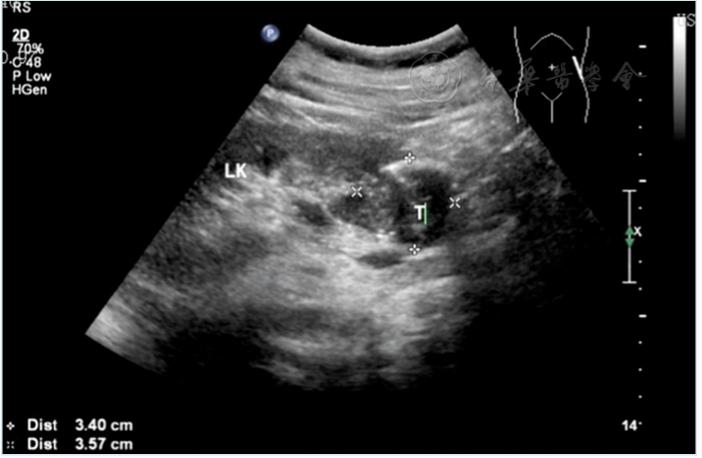

超声入门:肾结石超声诊断

1.3超声右肾结石0.4cm

长不大的肾肿瘤 - 超声医学讨论版 - 爱爱医医学论坛

一例后肾腺瘤超声表现病例分析

各类肾脏病超声图像表现